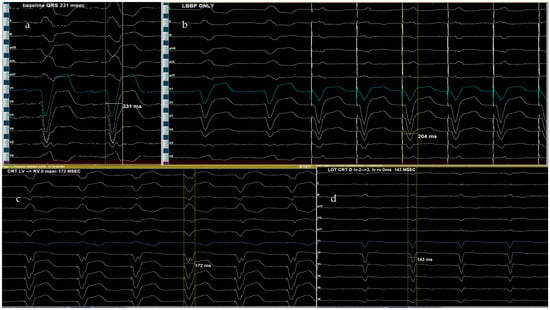

9. Our Center’s Experience—Proposed Implantation Algorithm